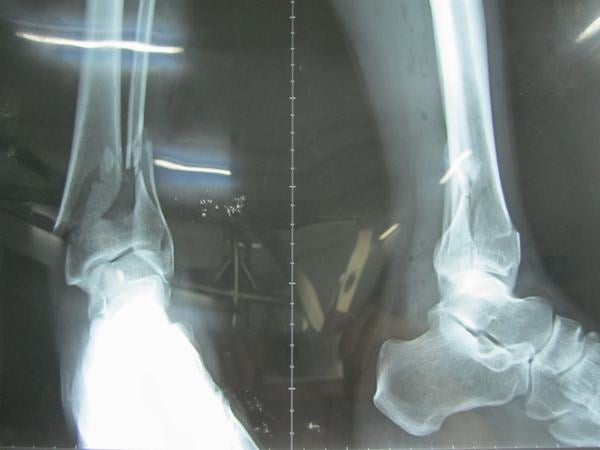

Hỏi đáp về rạn xương mác cẳng chân

Rạn xương mác cẳng chân là một chấn thương rất thường gặp và gây ảnh hưởng tới khả năng vận động, đi lại, sinh hoạt. Nếu không điều trị đúng cách sẽ để lại di chứng nặng nề. 1. Vì sao bị rạn xương mác cẳng chân? Rạn, nứt xương là một dạng của gãy […]